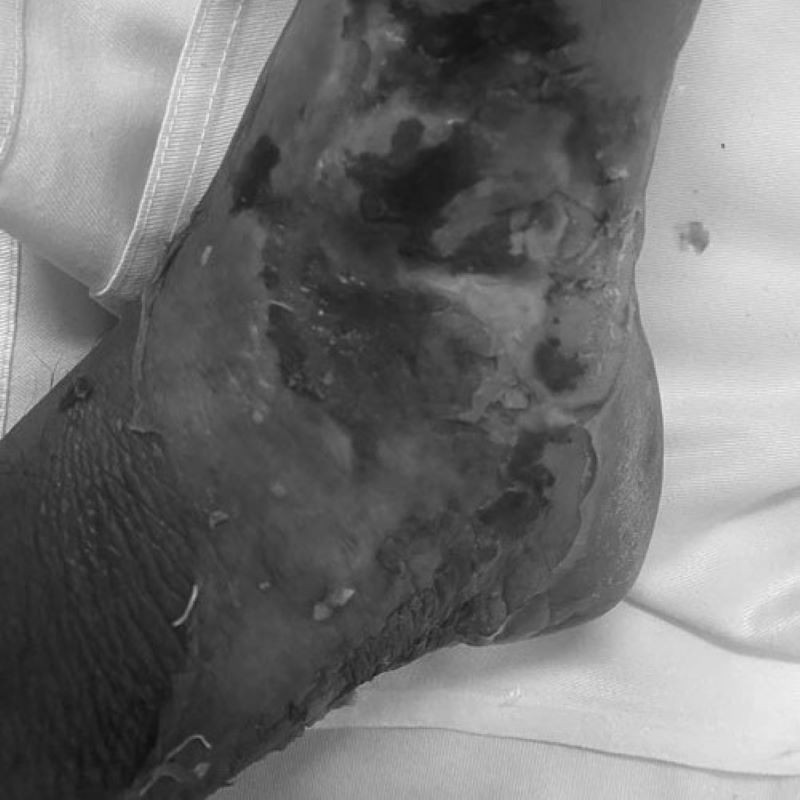

Bị rắn cắn vào vùng cổ chân, thay vì đến bệnh viện để có hướng điều trị phù hợp người bệnh lại tự điều trị tại nhà bằng cách đắp thuốc nam. Hậu quả vết thương nhiễm trùng, phải đến bệnh viện cấp cứu.

Như trường hợp của một người đàn ông 53 tuổi (Quảng Yên – Quảng Ninh) vô tình bị rắn cắn. Sau khi tự đắp thuốc tại nhà, người bệnh phải đến Bệnh viện Việt Nam – Thụy Điển Uông Bí với vùng chân sưng tấy, nóng rát.

Các bác sĩ đã tiến hành xử trí vết thương, cắt lọc tổ chức hoại tử và điều trị kháng sinh tích cực để kiểm soát nhiễm trùng.

Chỉ đến khi vết thương có biểu hiện nặng sưng đỏ, chảy dịch... người bệnh mới đến bệnh viện để điều trị. Việc kéo dài thời gian như vậy sẽ khiến việc điều trị phức tạp hơn, người bệnh phải chịu nhiều đau đớn và kéo theo rất nhiều hệ lụy.